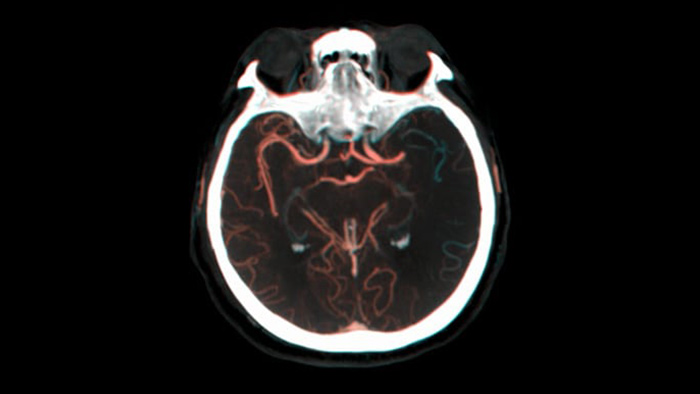

Tres SmartCT

Visualización similar a una TC

SmartCT Soft Tissue  genera una visualización de los tejidos blandos similar a la de una TC y apoya el diagnóstico del accidente cerebrovascular de tres maneras. Una exploración sin contraste ayuda a detectar los cambios isquémicos tempranos. Una exploración de fase temprana ayuda a identificar la oclusión proximal. Una exploración con contraste de fase tardía ayuda a detectar colaterales.

Ver llenado colateral

Visualización del llenado colateral

La vista dual para ver los volúmenes de TC de haz cónico de fase temprana y tardía uno al lado del otro mejora la identificación de la penumbra y permite la visualización del relleno colateral.